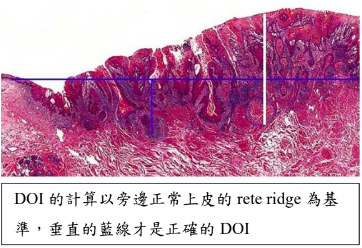

TNM staging

- Tumor: 原發性腫瘤(primary tumor)的大小和侵犯範圍

- 大小(cm)

- 深度 (DOI,mm)

TX: 無法評估Tis: carcinoma in situ

OSCC and HPV- OPSCC staging

- T

| DOI(mm) \ size(cm) | < 2 | 2~4 | > 4 |

|---|---|---|---|

| < 5 | T1 | T2 | T3 |

| 5~10 | T2 | T2 | T3 |

| >10 | ? | T3 | T3 |